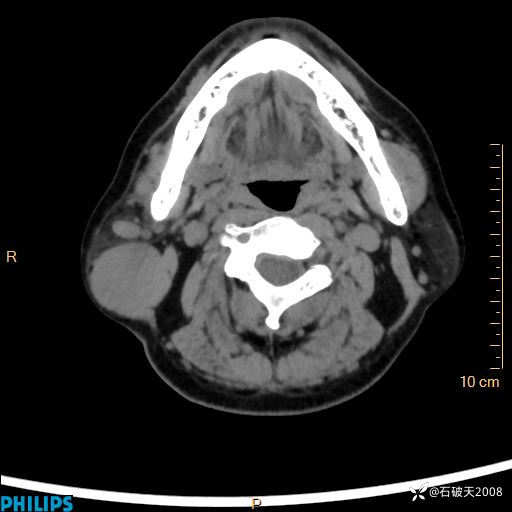

MIP